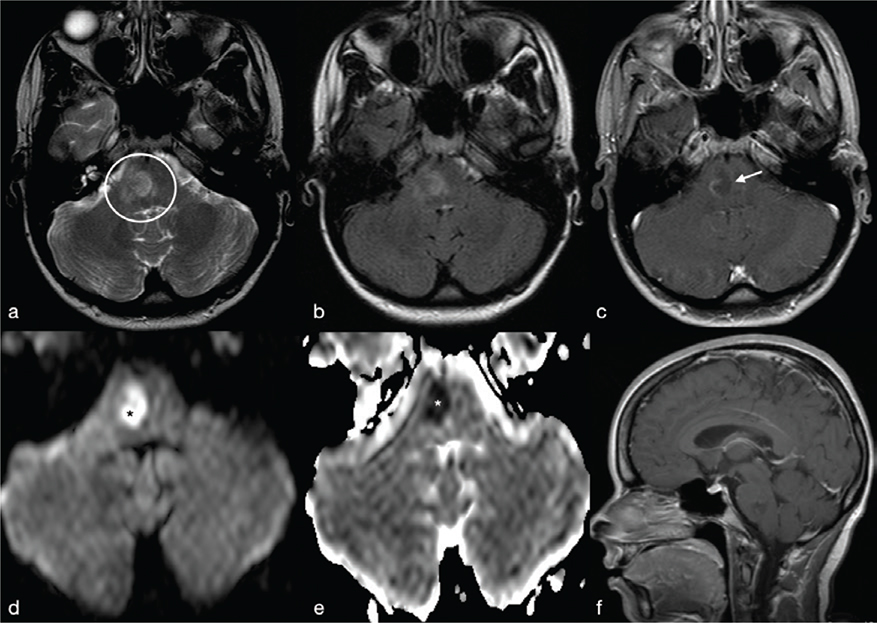

Fungal BA are rare and usually demonstrate low T2w signal in the centre and a ring-enhanced wall. Restricted diffusion may be seen in the capsule of the fungal abscess called “intracavitary projections.” Low ADC values are due to fungal organisms located at the periphery of the lesions and mucoid material.7 Opposite to pyogenic BA, fungal BA do not have the “dual rim” sign on SWI images but are characterised by a thick dark peripheral rim with multiple intralesional dark spots related to intralesional haemorrhage, typical in Aspergillus infection (Figure 15). Moreover, MRS may show lipid, lactate, amino acids and trehalose (3.6–8 ppm).15 In particular, trehalose has been observed in cryptococcosis.7

FIG 15. Fungal Brain Abscess (Aspergillus) in an Immunocompromised 44-Year-Old Man with Headache and Progressive Deterioration of Consciousness for 4 Days. A right parietal mass was observed in close proximity to the superior sagittal sinus with perifocal vasogenic oedema on T2w. (b, c) Spontaneous T1 shortening likely caused by xanthochromic fluid (extracellular methemoglobin) is present (b) with slight irregular enhancement after i.v. Gd administration (c). In fungal abscess, the rim of irregular hypointense signal on SWI, rather than haemoglobin breakdown products, may be consistent with the presence of elements with paramagnetic properties, such as iron or magnesium (d). DWI (e) and ADC maps (f) reveal heterogeneous signal with restricted diffusion in the lesional core and in the peripheral rim.